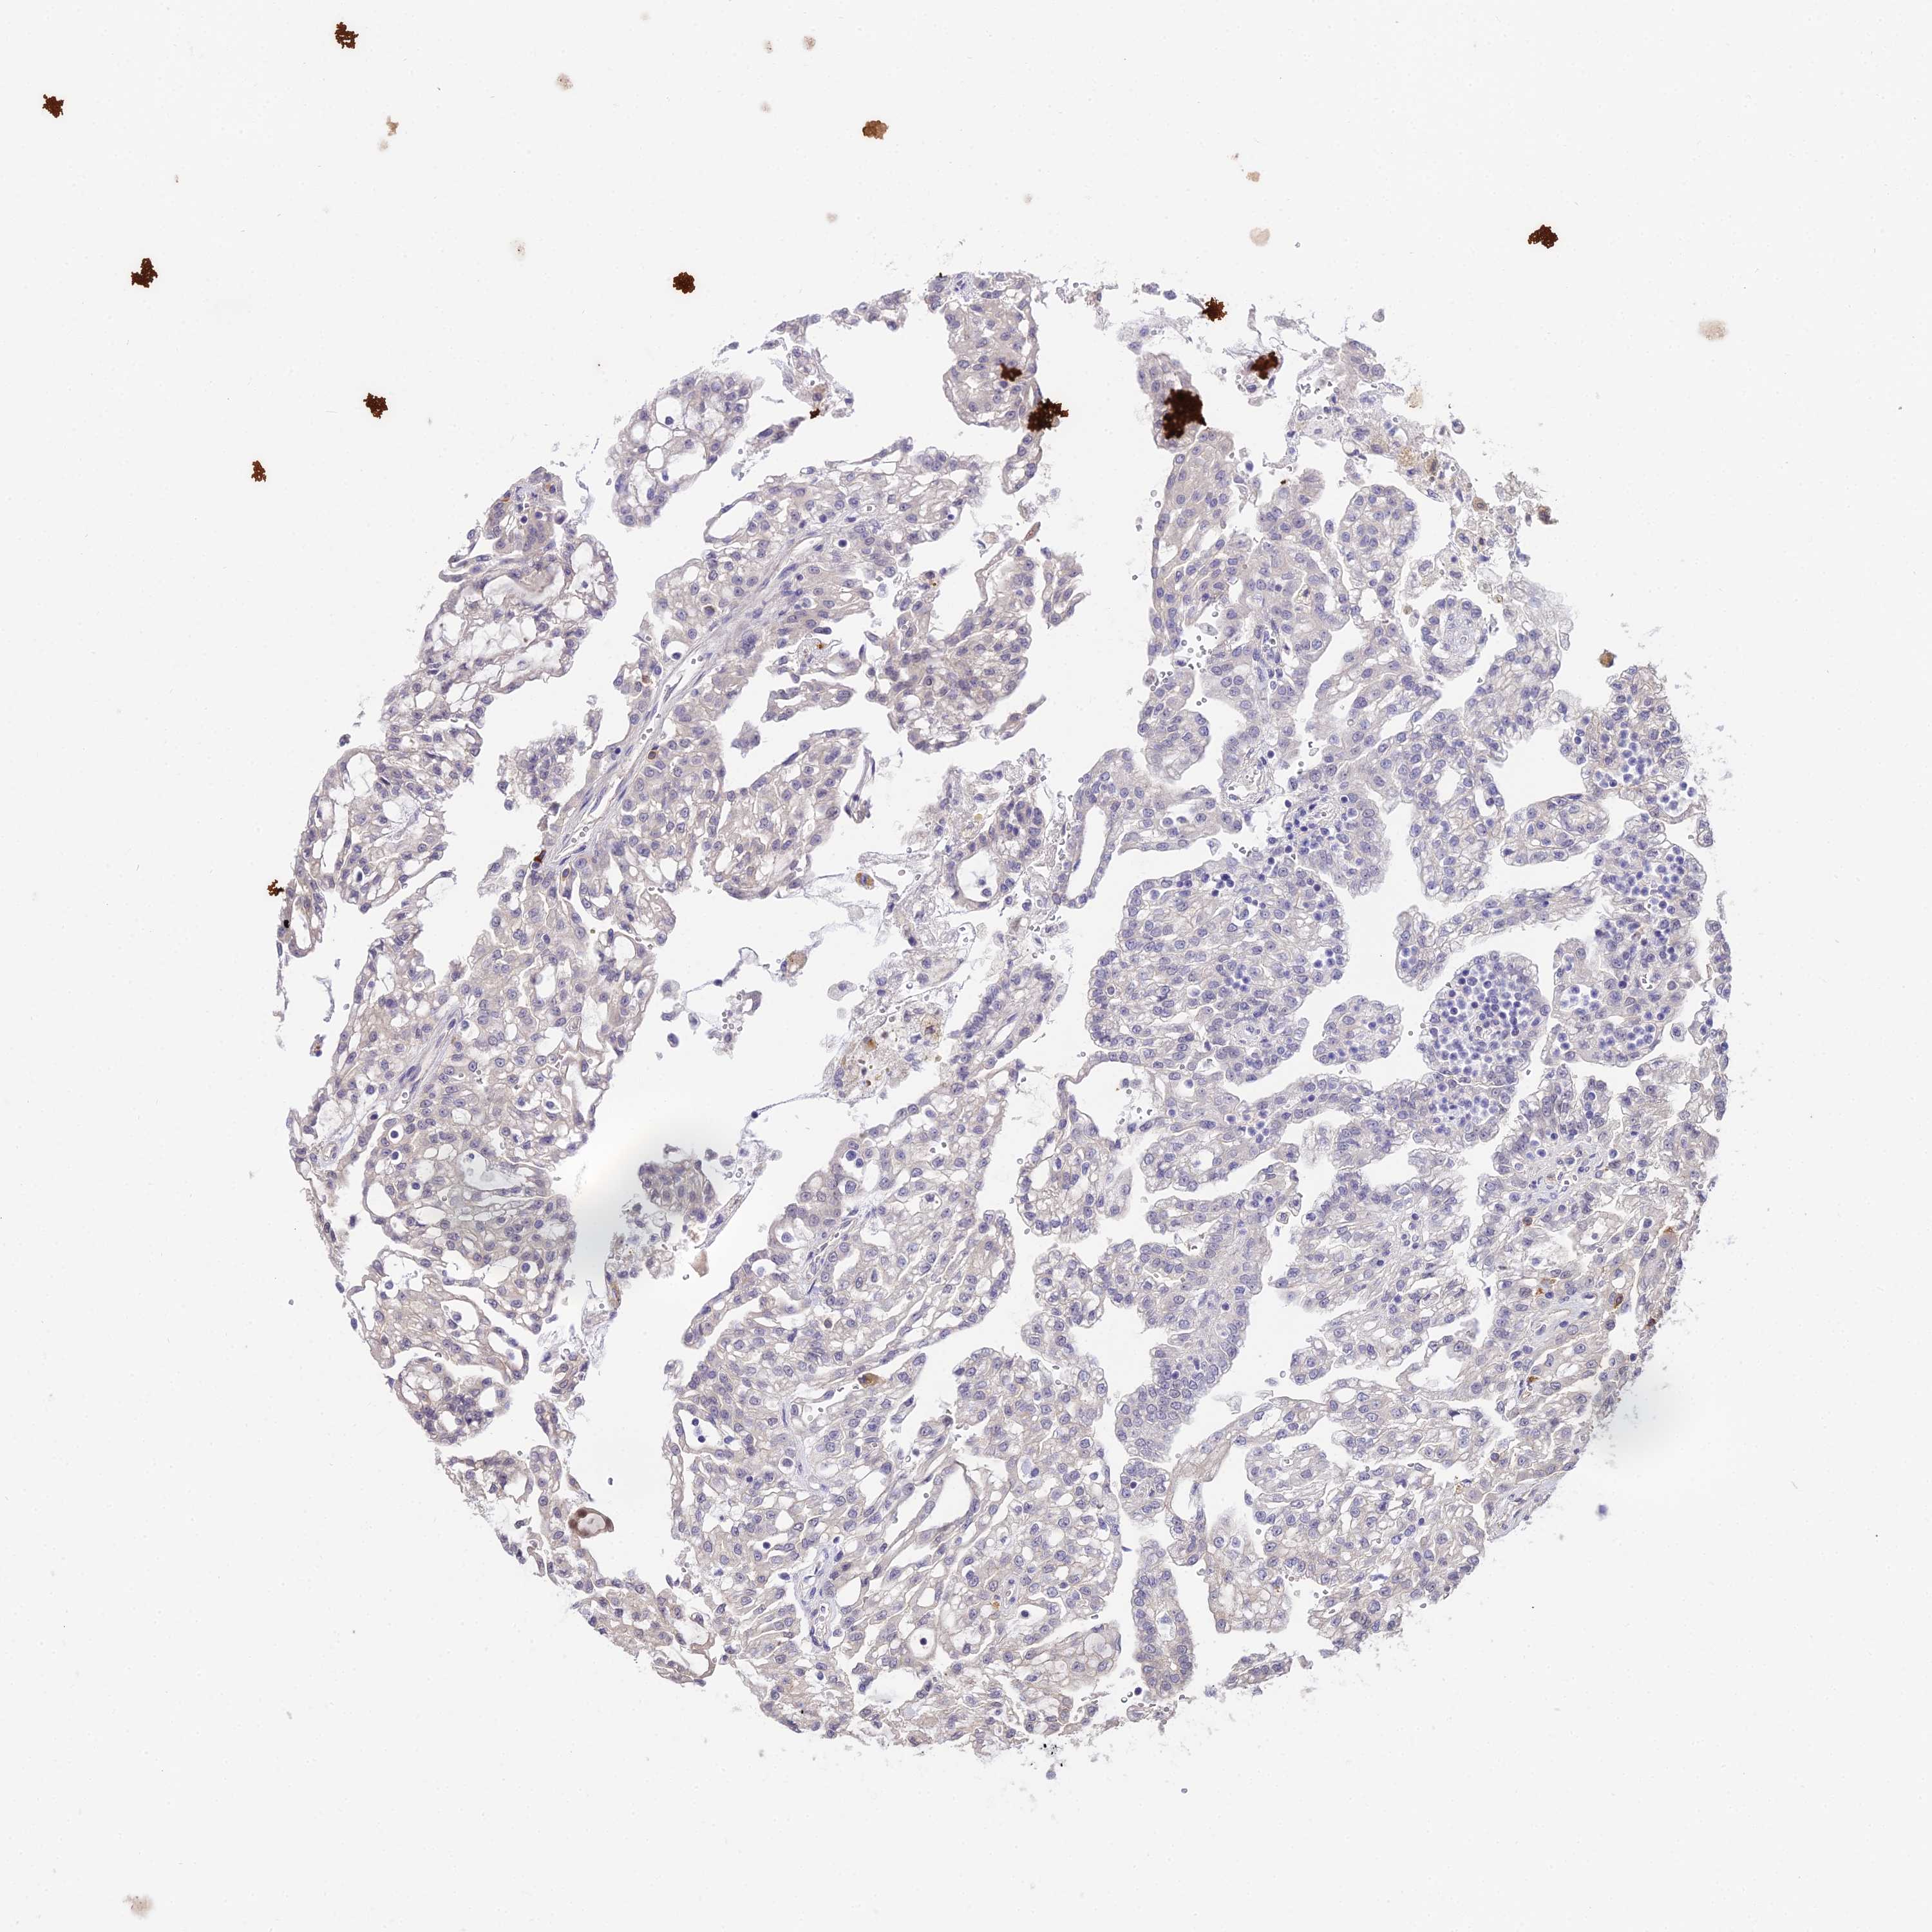

KIDNEY RENAL PAPILLARY CELL CARCINOMA (TCGA) - Interactive survival scatter ploti

The Survival Scatter plot shows the clinical status (i.e. dead or alive) for all individuals in the patient cohort, based on the same data that underlies the corresponding Kaplan-Meier plots. Patients that are alive at last time for follow-up are shown in blue and patients who have died during the study are shown in red.

The x-axis shows the expression levels (FPKM) of the investigated gene in the tumor tissue at the time of diagnosis. The y-axis shows the follow-up time after diagnosis (years). Both axes are complimented with kernel density curves demonstrating the data density over the axes. The top density plot shows the expression levels (FPKM) distribution among dead (red) and alive patients (blue). The right density plot shows the data density of the survived years of dead patients with high and low expression levels respectively, stratified using the cutoff indicated by the vertical dashed line through the Survival Scatter plot. This cutoff is automatically defined based on the FPKM cutoff that minimizes the p-score. The cutoff can be changed by dragging the vertical line or by entering a cutoff value in the square labeled "Current cut-off".

Under the Survival Scatter plot the p-score landscape (black curve; left axis) is shown together with dead median separation (red curve; right axis). Dead median separation is the difference in median mRNA expression between patients who have died with high and low expression, respectively. It is calculated as follows: median FPKM expression of dead patients with high expression - median FPKM expression of dead patients with low expression. This is intended to aid the user in visually exploring custom cutoffs and the associated p-scores and dead median separation.

Individual patient data is displayed and can be filtered by clicking on one or more of the category buttons on the top of the page. Categories describing expression level and patient information include: high, low, alive, dead, female, male and tumor stages. The scale of the x-axis can be toggled between linear and log-scale by clicking on the "x log" button. Mouse-over function shows TCGA ID, patient information and mRNA expression (FPKM) for each patient.

& Survival analysisi

Kaplan-Meier plots summarize results from analysis of correlation between mRNA expression level and patient survival. Patients were divided based on level of expression into one of the two groups "low" (under cut off) or "high" (over cut off). X-axis shows time for survival (years) and y-axis shows the probability of survival, where 1.0 corresponds to 100 percent.

POLR2I is not prognostic in Kidney Renal Papillary Cell Carcinoma (TCGA)